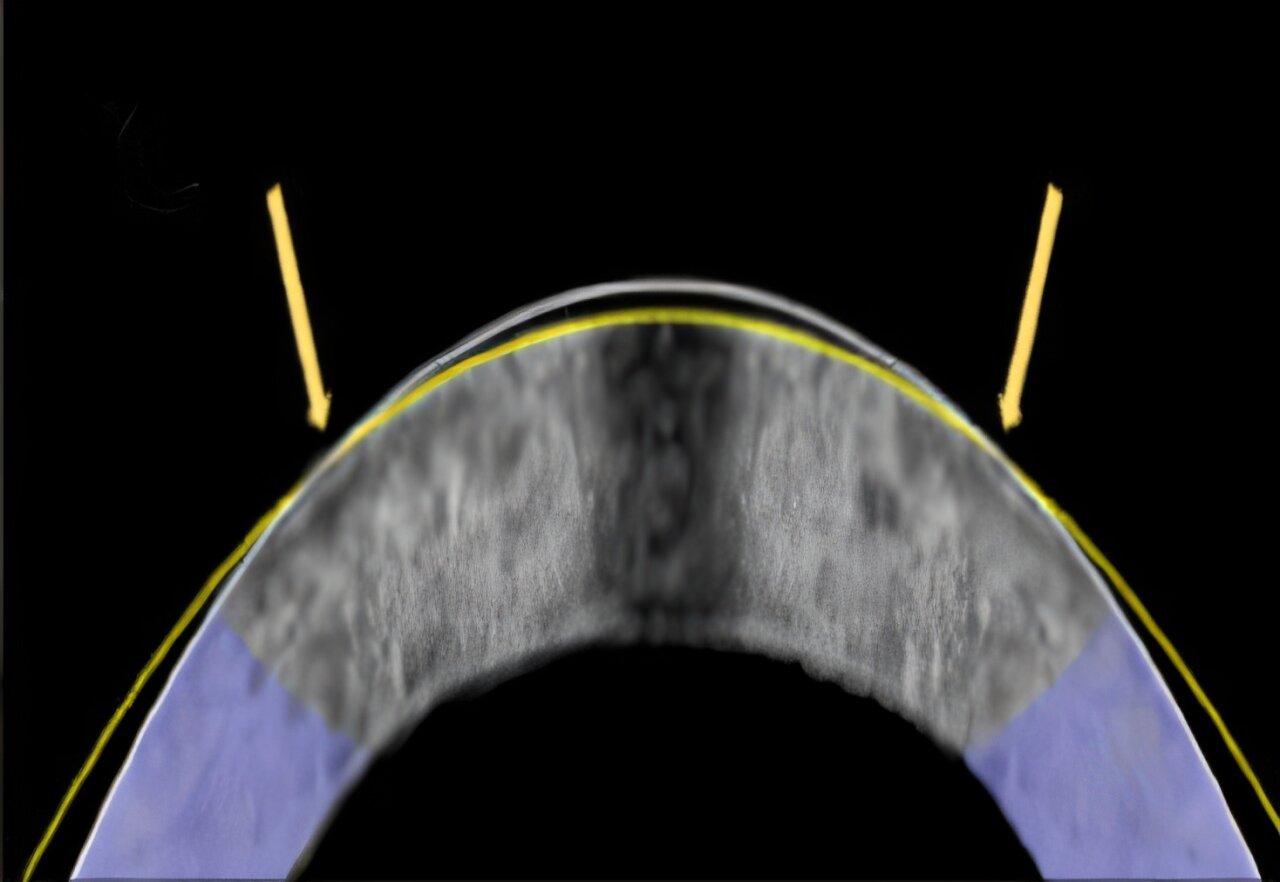

电机械重塑技术成功地将这只兔子的角膜(如横截面所示)从其原始形状(白色线)重塑为矫正后的形状(黄色线)。

在最新实验中,他们制作了一种特制的铂金“隐形眼镜”,将其覆盖在浸泡于盐水(模拟眼泪环境)中的兔眼上。这个镜片既是模具,也是电极。当研究人员在镜片上施加微小电压时,角膜的酸碱环境发生改变,短短一分钟后,角膜曲率便服帖地“印”出了镜片的弧度。这个过程所需时间和LASIK差不多,但无需昂贵的设备,也完全没有切割。

他们在12只兔眼上重复了实验,其中10只是模拟近视的角膜。结果显示,所有“近视眼”在处理后都获得了目标聚焦力,相当于视力得到改善。细胞在过程中并未受损,因为研究人员严格控制了酸碱梯度。更令人惊喜的是,在其他实验中,这一方法甚至能消除部分由化学损伤引起的角膜混浊——目前这种情况只能通过角膜移植来解决。